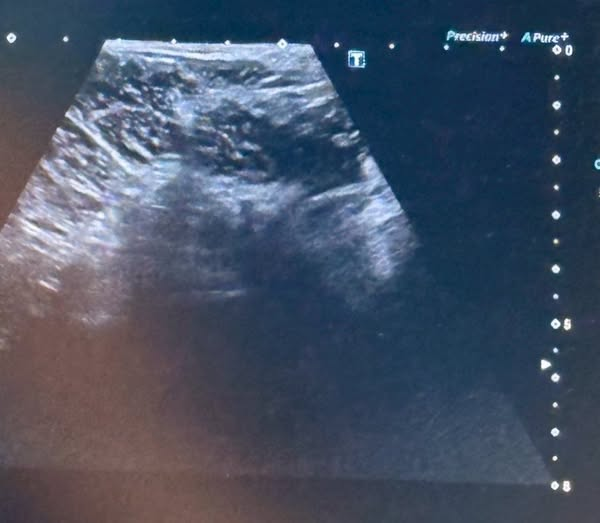

日本初となる股関節へのラジオ波末梢神経焼灼療法(ラジオ波治療)が成功いたしました。

本治療は自費診療となりますが、股関節だけでなく、腰・肩・臀部・足関節・関節の拘縮など、さまざまな部位の痛みに対しても、松岡理事長独自の手技によるラジオ波治療をご提供しております。

現在までに、ラジオ波治療の手術症例数は570例に達しております。